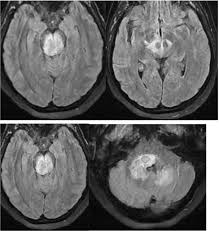

eye of the tiger sign

globus pallidus T2 hypointensity with central hyperintensity

PKAN

iron deposition disorder